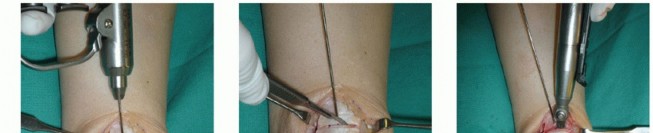

Make a longitudinal incision centered over the medial malleolus ( TECH FIG 1A ). Anterior ankle arthrotomy

Identify the joint line ( TECH FIG 1B ).

Visualize the anterior talus and possibly anterior OLT ( TECH FIG 1C ).

TECH FIG 1 • A. Medial approach is similar to that for open reduction and internal fixation for a medial malleolar fracture. B,C. Anterior ankle arthrotomy. B. Locating joint and performing the medial capsulotomy. C. Medial talar dome visible through the arthrotomy with capsule retracted. This defines the anterior margin for the osteotomy. Rarely, the OLT may be accessed via arthrotomy alone, but this is more common for lateral lesions.

Open the flexor retinaculum (

TECH FIG 1D

).

Identify and protect the posterior tibial tendon (PTT) ( TECH FIG 1E ).

Predrill the intended screw holes for fixation of the osteotomy.

Two parallel drill holes in the same orientation are typically used for open reduction and internal fixation of a medial malleolar fracture ( TECH FIG 1F ).

Consider tapping the screw holes as well (traditional malleolar screws are not self-tapping) ( TECH FIG 1G ).

TECH FIG 1 •

(continued)

D,E. Defining posterior tibia for the osteotomy. D. Opening the flexor retinaculum. E. Identifying the PTT (to be protected during the osteotomy). F,G. Predrilling the medial malleolus. F. Drill bit directed as it would be for medial malleolar screws for open reduction and internal fixation of a medial malleolar fracture. G. Tap used for screws that are not self-tapping. Trajectory of the oblique osteotomy